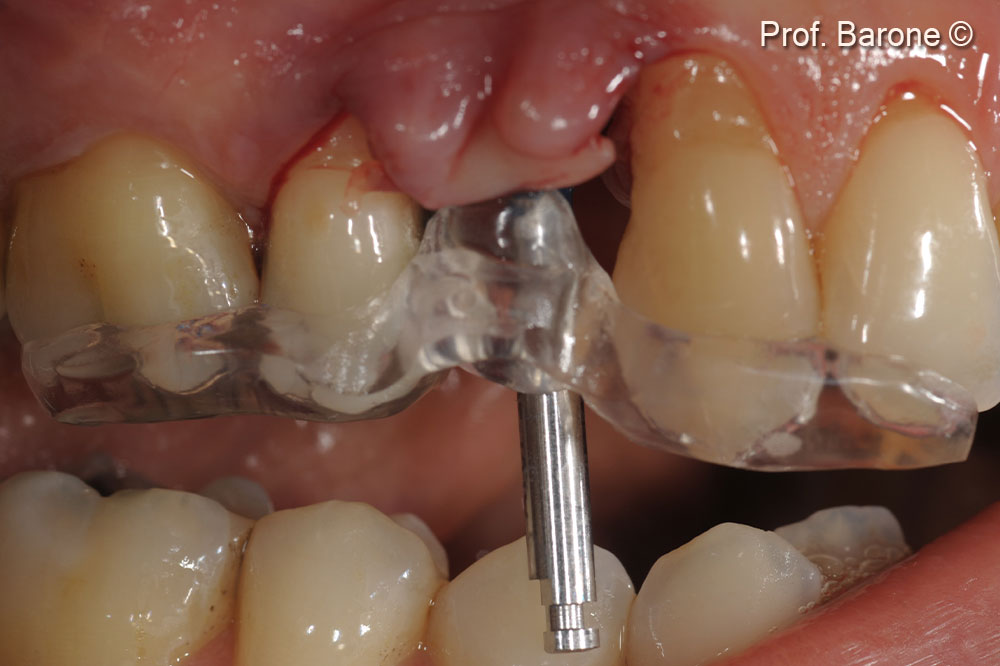

Clinical lateral view at implant placement (16 weeks after socket grafting) with a surgical guide